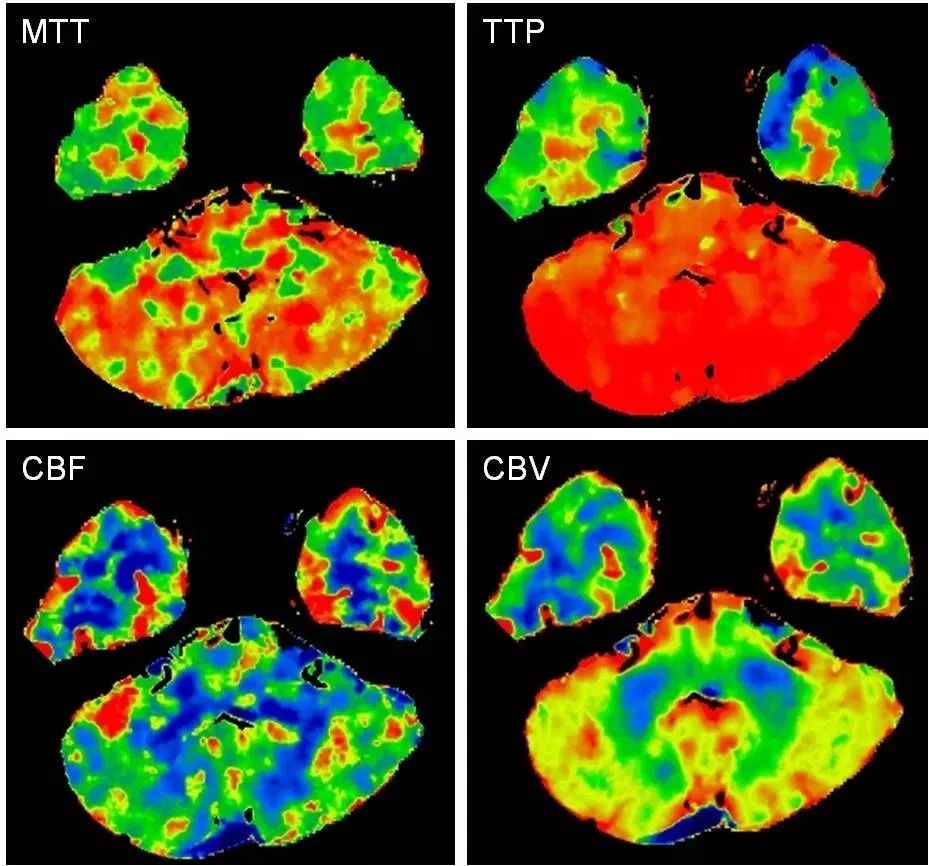

头部CTA+CTP:右椎动脉V4段长段重度狭窄,左椎动脉V3段闭塞,基底动脉近端见开窗(图5);后循环分布区低灌注(图6)。